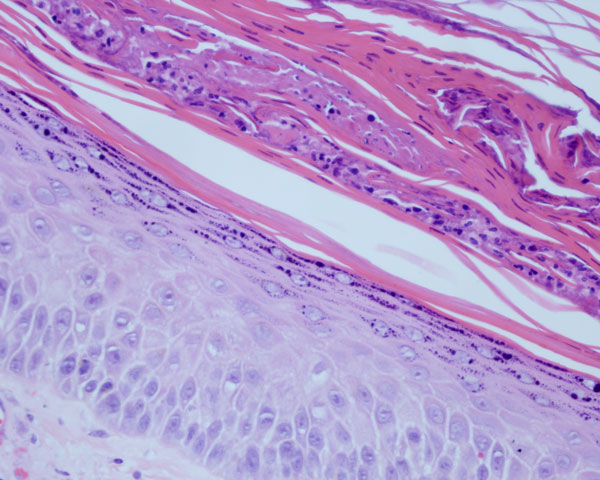

Sandwich sign refers to the presence of two different types of keratinisation in the stratum corneum, one beneath the other, in a parallel manner. Usually, there is an upper zone of orthokeratosis with underlying parakeratosis.

This is a clue to the presence of a dermatophyte and should prompt a careful search. PAS stain is mandatory. The fungal hyphae are commonly found in the orthokeratotic area, as the parakeratosis would imply a rapid turnover and hostile soil for its growth.